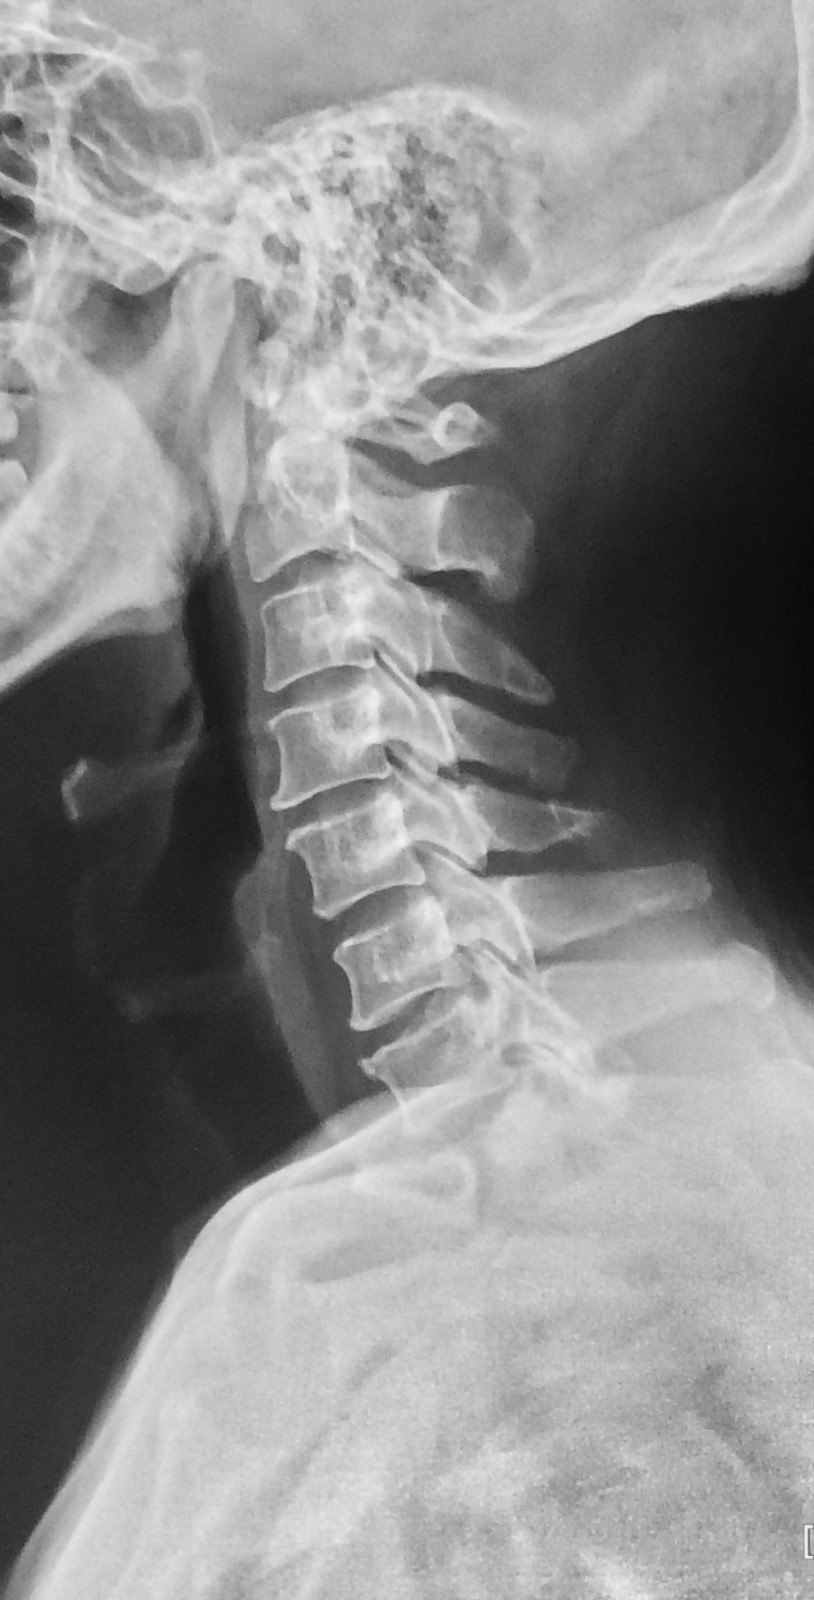

颈椎黄韧带骨化症

颈椎间盘突出伴黄韧带肥厚后纵韧带严重骨化

怀疑颈椎病去医院拍片,发现后方项韧带钙化,有什么意义?

后纵韧带钙化:由于后纵韧带上有钙盐沉积及骨化, 使颈椎管的矢状径